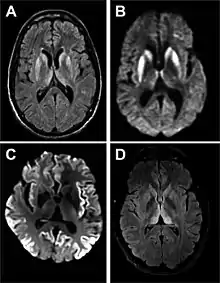

Imaging of the brain may be performed during medical evaluation, both to rule out other causes and to obtain supportive evidence for diagnosis. Imaging findings are variable in their appearance, and also variable in sensitivity and specificity.[43] While imaging plays a lesser role in diagnosis of CJD,[44] characteristic findings on brain MRI in some cases may precede onset of clinical manifestations.[45]

Brain MRI is the most useful imaging modality for changes related to CJD. Of the MRI sequences, diffuse-weighted imaging sequences are most sensitive.[46] Characteristic findings are as follows:

- Focal or diffuse diffusion-restriction involving the cerebral cortex and/or basal ganglia. In about 24% of cases DWI shows only cortical hyperintensity; in 68%, cortical and subcortical abnormalities; and in 5%, only subcortical anomalies.[47] The most iconic and striking cortical abnormality has been called "cortical ribboning" or "cortical ribbon sign" due to hyperintensities resembling ribbons appearing in the cortex on MRI.[48] The involvement of the thalamus can be found in sCJD, is even stronger and constant in vCJD.[49]

- Varying degree of symmetric T2 hyperintense signal changes in the basal ganglia (i.e., caudate and putamen), and to a lesser extent globus pallidus and occipital cortex.[44]